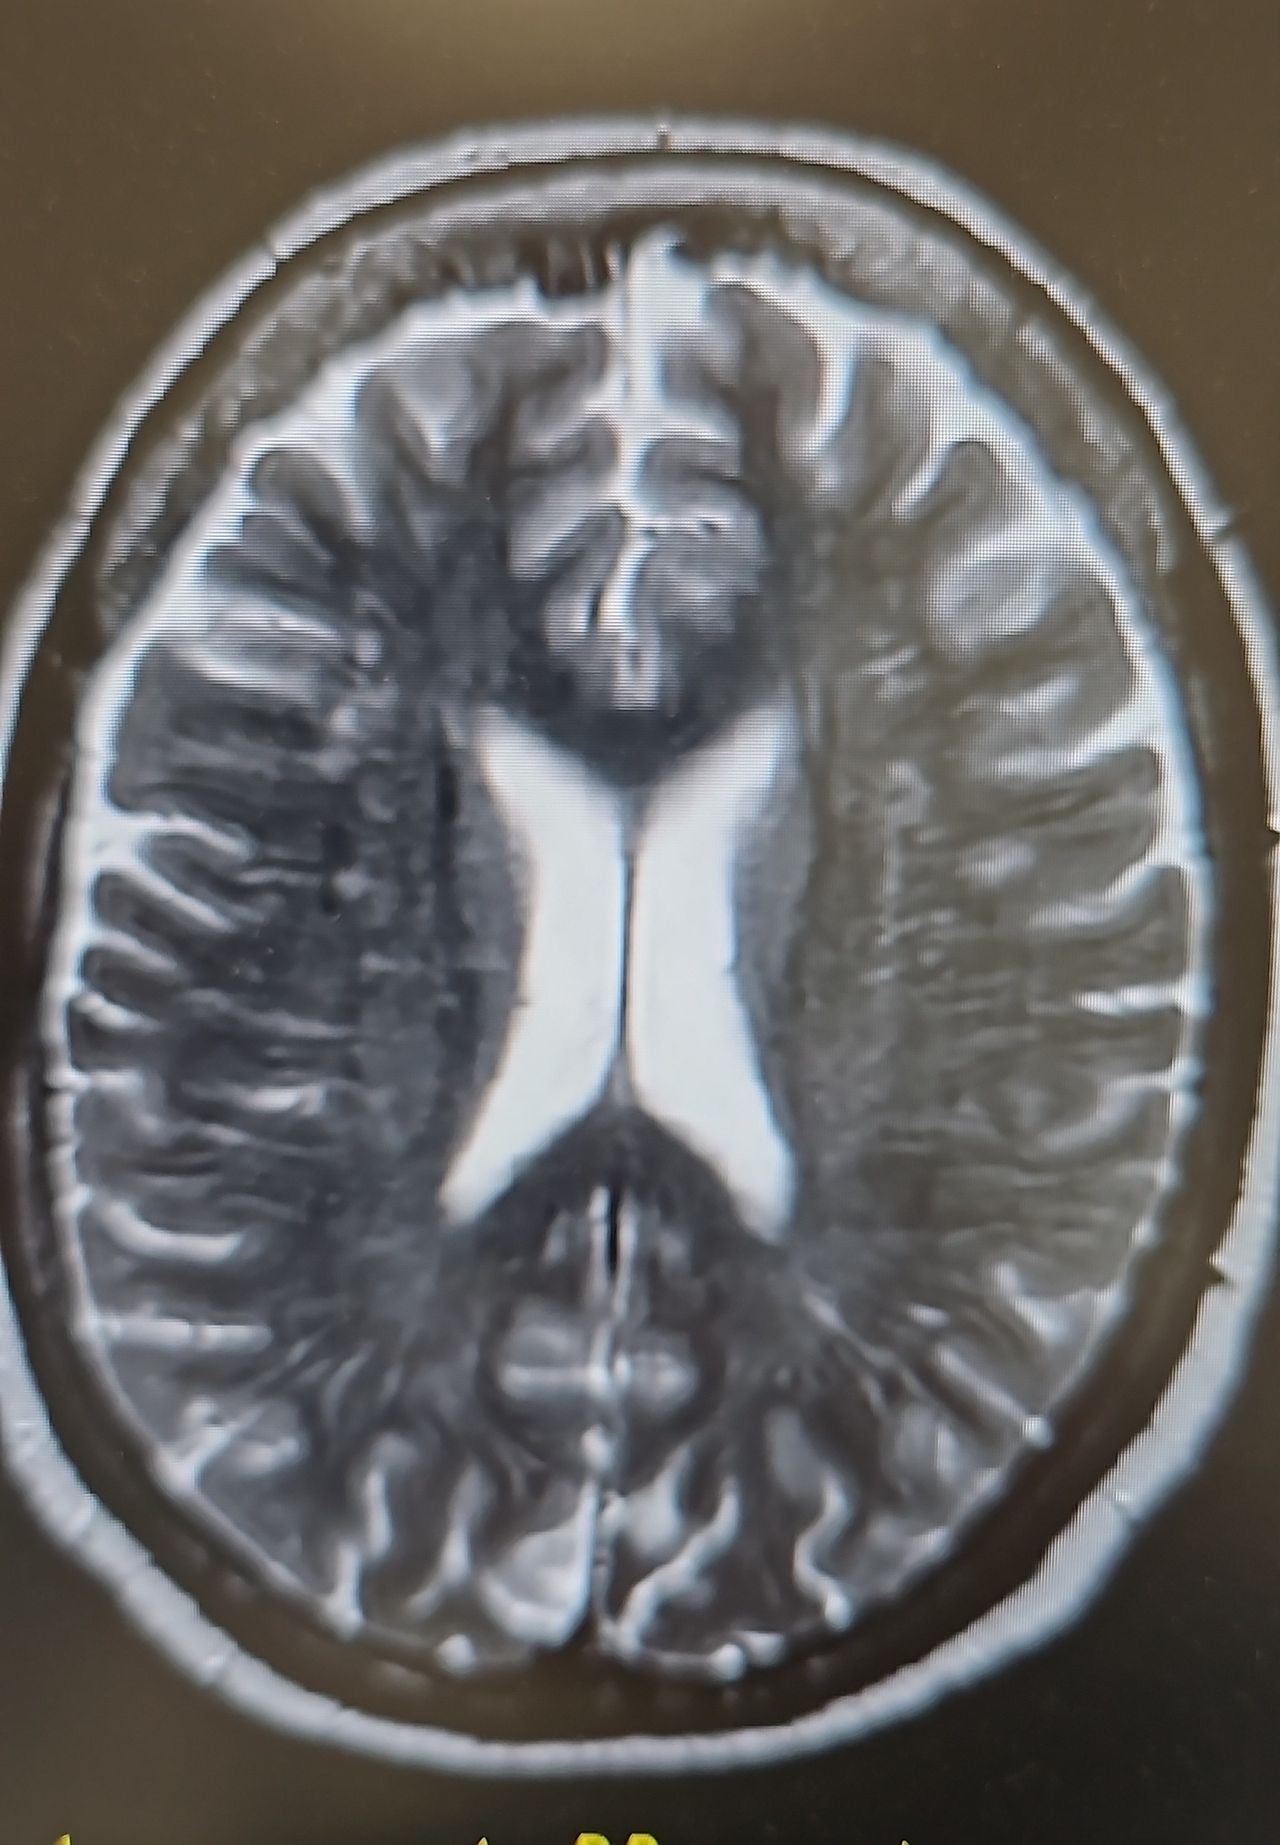

Foto e video